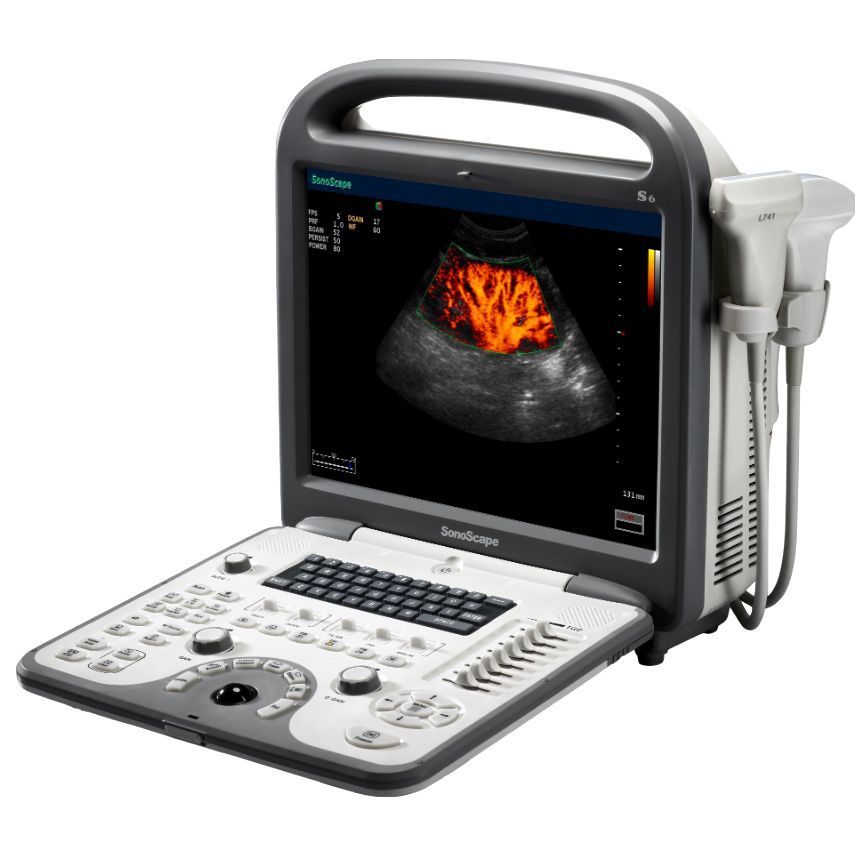

УЗИ аппараты

УЗИ аппараты

УЗИ аппараты

УЗИ аппараты

УЗИ аппараты

УЗИ аппараты

УЗИ аппараты

УЗИ аппараты

УЗИ аппараты

УЗИ аппараты

УЗИ аппараты

УЗИ аппараты

УЗИ аппараты

УЗИ аппараты